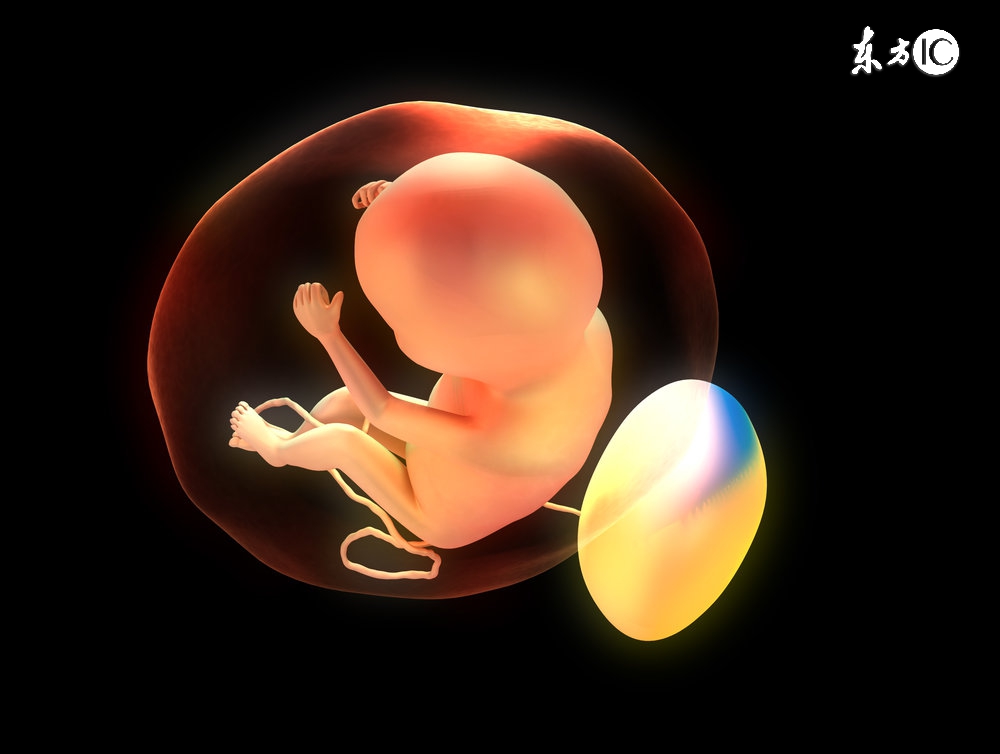

孕期B超是在怀孕之后,孕妈妈一般都会定期的去医院做B超,检测宝宝的生长发育情况。这是一项为了检测胎儿健康发育的常规检查之一。

其实B超还真的不是万能,有很多是检测不出来。因为胎内的情况复杂,而且加上B超时也会因胎儿动作、孕期阶段的不同而存在各种盲点。

B超能检查出来啥

孕早期(1-3个月)

1、检查目的:

确定孕周,确定是否多胎妊娠,确定胎儿发育情况。